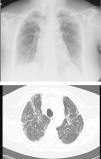

However, BOS is not the only manifestation of chronic rejection. Patterns other than obstruction that are not included under BOS have been described. Chronic lung allograft dysfunction (CLAD) is probably a better way of defining a chronic decline in FEV1 than BOS. In recent years, it has been observed that CLAD is a heterogeneous condition defining different phenotypes, including, in addition to the classic BOS, other patterns that include partial reversibility to airway obstruction, restrictive ventilatory deterioration and changes in lung parenchyma.22 Neutrophilic reversible allograft dysfunction (NRAD) is characterised by airway neutrophilia (bronchoalveolar lavage [BAL]>15% neutrophils) and functional improvement (>10% in FEV1) after azithromycin treatment.23–26 Restrictive allograft syndrome (RAS) comprises 25%–35% of CLAD and is defined as a fall from baseline in total lung capacity (TLC) greater than 10% and fibrosis, predominantly in the upper lobes (Fig. 4). It progresses more rapidly and has a poorer prognosis than BOS.27,28

Pulmonary fibrosis changes in upper lobes of a patient diagnosed with restrictive allograft syndrome (chest X-ray and chest CT).